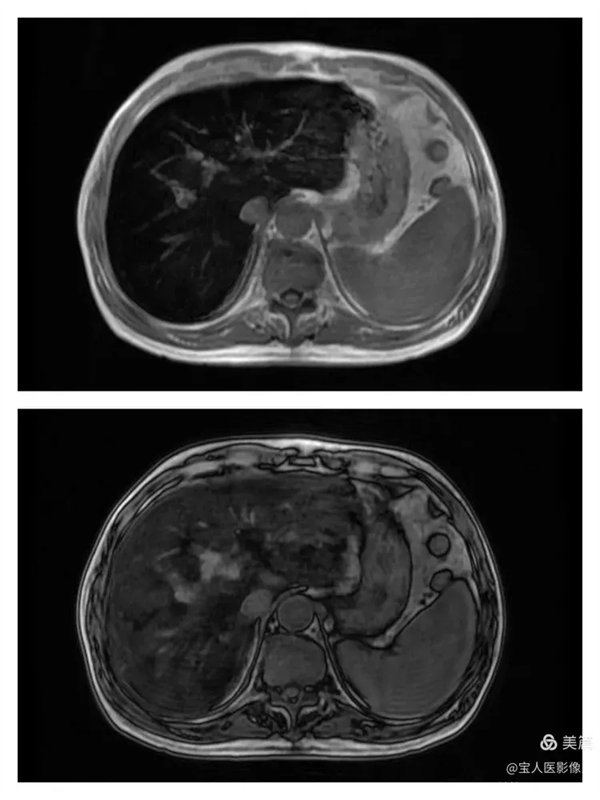

T1WI圖,軸位,肝實(shí)質(zhì)信號(hào)仍呈明顯低信號(hào)。

同、反相位,肝實(shí)質(zhì)信號(hào)反相位略不均勻升高。